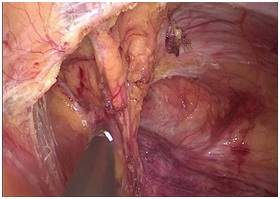

手术图片

腹腔镜直肠癌根治术

腹腔镜胃癌根治术